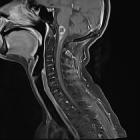

Thorakale

Myelopathie nach Bestrahlung bei ossär metastasiertem Mammakarzinom. Links T1, rechts T2 sagittal: man erkennt die fettige Degeneration des knöchernen Markraums der bestrahlten Wirbel und besser in T2 als in T1 die zentrale, spindelförmige Myelopathie im unteren Bereich des Bestrahlungsfeldes.